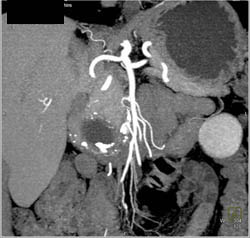

Pseudocyst